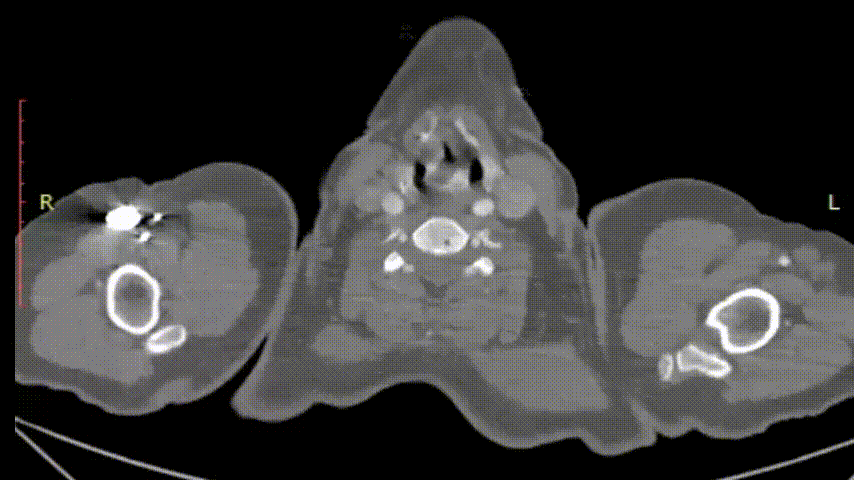

★ Case 4

男性,71岁,间断胸痛半年,加重7+天

高血压1+年,收缩压最高160+ mmHg

既往史和手术史:保守治疗1+月,弓部血肿增厚,胸痛加重

夹层动脉瘤CTA:主动脉夹层(非A非B型),累及主动脉弓至腹腔干发出平面以上腹主动脉,真腔小,假腔大;主动脉弓及左颈总动脉、左锁骨下动脉近端管径增粗,合并壁内血肿

术前影像

股-升主动脉支架

颈-无名动脉+左颈总动脉支架

股-弓部+左锁骨下动脉支架

术后复查